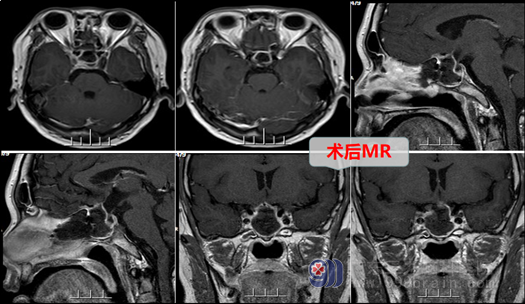

结合患者症状、体征、头颅MR检查,本院头MRI结果示:鞍区病灶--垂体瘤,蓝先生症状明显,有内分泌紊乱,有手术指针。欧阳教授与神经外十科医疗小组分析、讨论后决定:实施手术—“神经内镜下经鼻腔-蝶窦垂体病损切除术” 。术中,在内镜直视下分开鼻中隔粘膜,磨开鞍底骨质,形成鞍底骨窗约1.5cm大小。钩刀“+字型”全层切开硬脑膜。见肿瘤灰白色,质软,正常垂体组织位于左后方,全切肿瘤,鞍膈塌陷,双侧海绵窦内侧壁无肿瘤残留,正常垂体保护良好,无脑脊液漏。术后第二天,患者神志清醒,查体合作,语言清晰,问答切题。

现蓝先生已健康出院,宣教其三个月后复查,目前蓝先生自诉男性功能受损问题已经得到解决,有完全恢复了他重回幸福生活的信心。所以外十科医生提醒市民:一旦出现内分泌功能紊乱,要到专科医院看病,一旦确诊病因为垂体瘤,应找专业医生尽快解决,别一拖再拖,病情拖久了,痛苦的终归是患者。